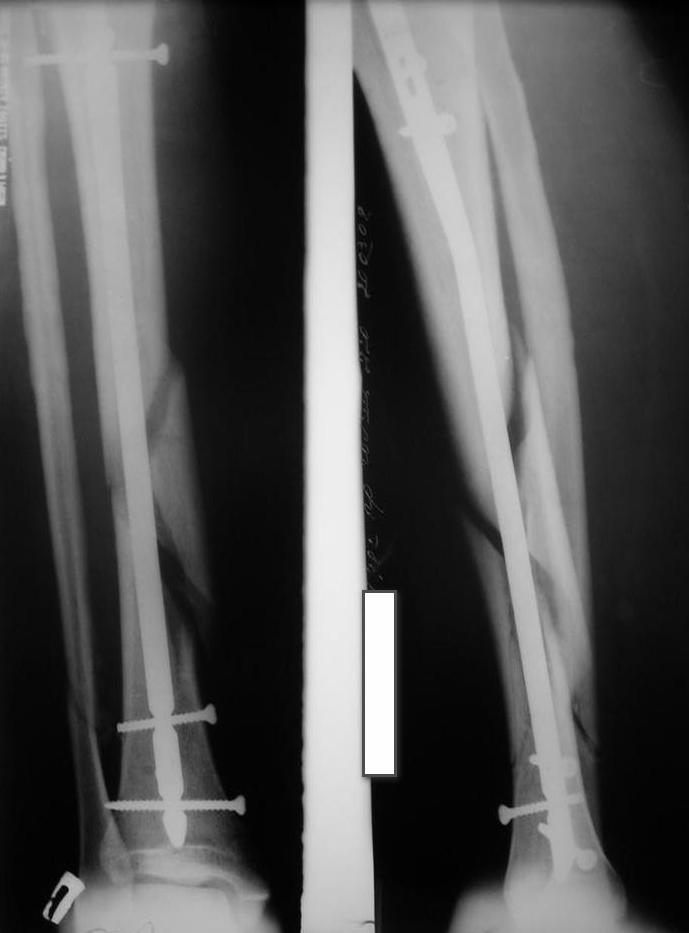

У нас был молодой пациент М.(26лет), травма 25 января 2009г, катался на лыжах и получил травму. Поступил к нам в отделение в экстренном порядке. При обследованиии выявлен закрытый винтоообразный оскольчатый перелом правой большеберцовой кости и косой перелом малоберцовой кости на границе средней и нижней трети. Выполнен интрамедуллярный блокируемый синтез большеберцовой кости, оси и длина конечности восстановлена. После операции пациент ходил с полной нагрузкой. Через 3 месяца на контрольных рентгенограммах сращения нет, динамизации не выполняли, так как оскольчатый перелом.(снимки в динамике прилагаются). Посоветуйте, что в данном случае делать наиболее целесообразно?

Отсутствие уверенных признаков сращения неделям к 8 - надо динамизировать. Тут уже 3,5 мес., есть щель из-за смещения по длине. Дальнейшее консервирование ситуации тут не решает никаких проблем, а вот создать их может. Динамизация с нагрузкой и диастаз уменьшит, и репаративный процесс "освежит".

Мне кажется, что необходимо выполнить динамизацию, одновременно выполнив остеотомию малоберцовой кости, т.к. у нее консолидация есть. В дальнейшем ходьба с дополнительной опорой и потепенным увеличением нагрузки около 25% в неделю с выходом до полной на 4-й неделе.

Господа,никаких признаков консолидации нет.Если где-то кажется,то это только за счет укладки(все снимки по-моему с разной укладкой).

По-моему, оптимальное решение уже прозвучало дважды: динамизация+остеоклазия(остеотомия) малоберцовой.